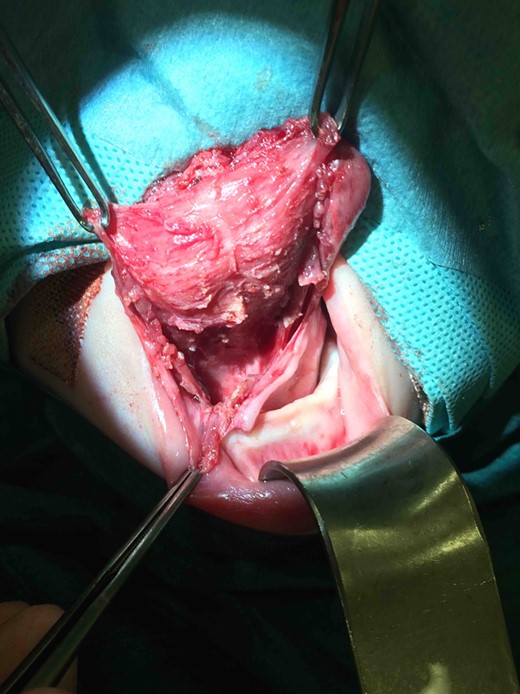

Clinic follow-up was expedited at age 5 weeks, as the cyst had increased rapidly in the preceding 10 days, resulting in impaired feeding. On examination, there was considerable swelling of the anterior tongue and floor of mouth, and the tongue was pushed superiorly against the hard palate and anteriorly, protruding past the lips. Interestingly there was no airway compromise. Fifteen millilitres of grey-brown fluid were aspirated from the cyst, which provided immediate reduction in swelling and improvement in feeding. It was planned to review the baby in 3 weeks with a view to future surgical excision, but to await microscopy and culture of the fluid and allow the neonate to grow further. Culture of the fluid showed no bacterial growth. However, at follow-up the cyst had re-collected to fill the entire oral cavity. Again there were no signs of airway compromise. Twenty millilitres of fluid were aspirated and the patient was booked for urgent surgical excision of the cyst. A horizontal sublingual incision above the submandibular duct openings was performed. The submandibular ducts and lingual nerves were identified and preserved. A cyst measuring 48 mm × 20 mm × 5 mm was excised, which extended up to the foramen caecum posteriorly (Figs 2–4). The defect was closed with vicryl rapide 4/0, and a small opening was left anteriorly and posteriorly to facillitate drainage. Histology showed that the cyst wall was lined by stratified squamous epithelium in some areas and bundles of smooth muscle in others. Additionally, there were small cystic structures lined by mucin-producing columnar cells. These appearances were consistent with the clinical diagnosis of a cystic thyroglossal duct remnant.

Pre-operative photograph of superior aspect of tongue demonstrating significant tongue swelling, resulting in the tongue protruding past the lips.